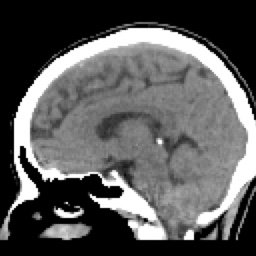

SIMPLE FINO SAG (9) 75 images

ARTERIAL FINO SAG (11) 78 images